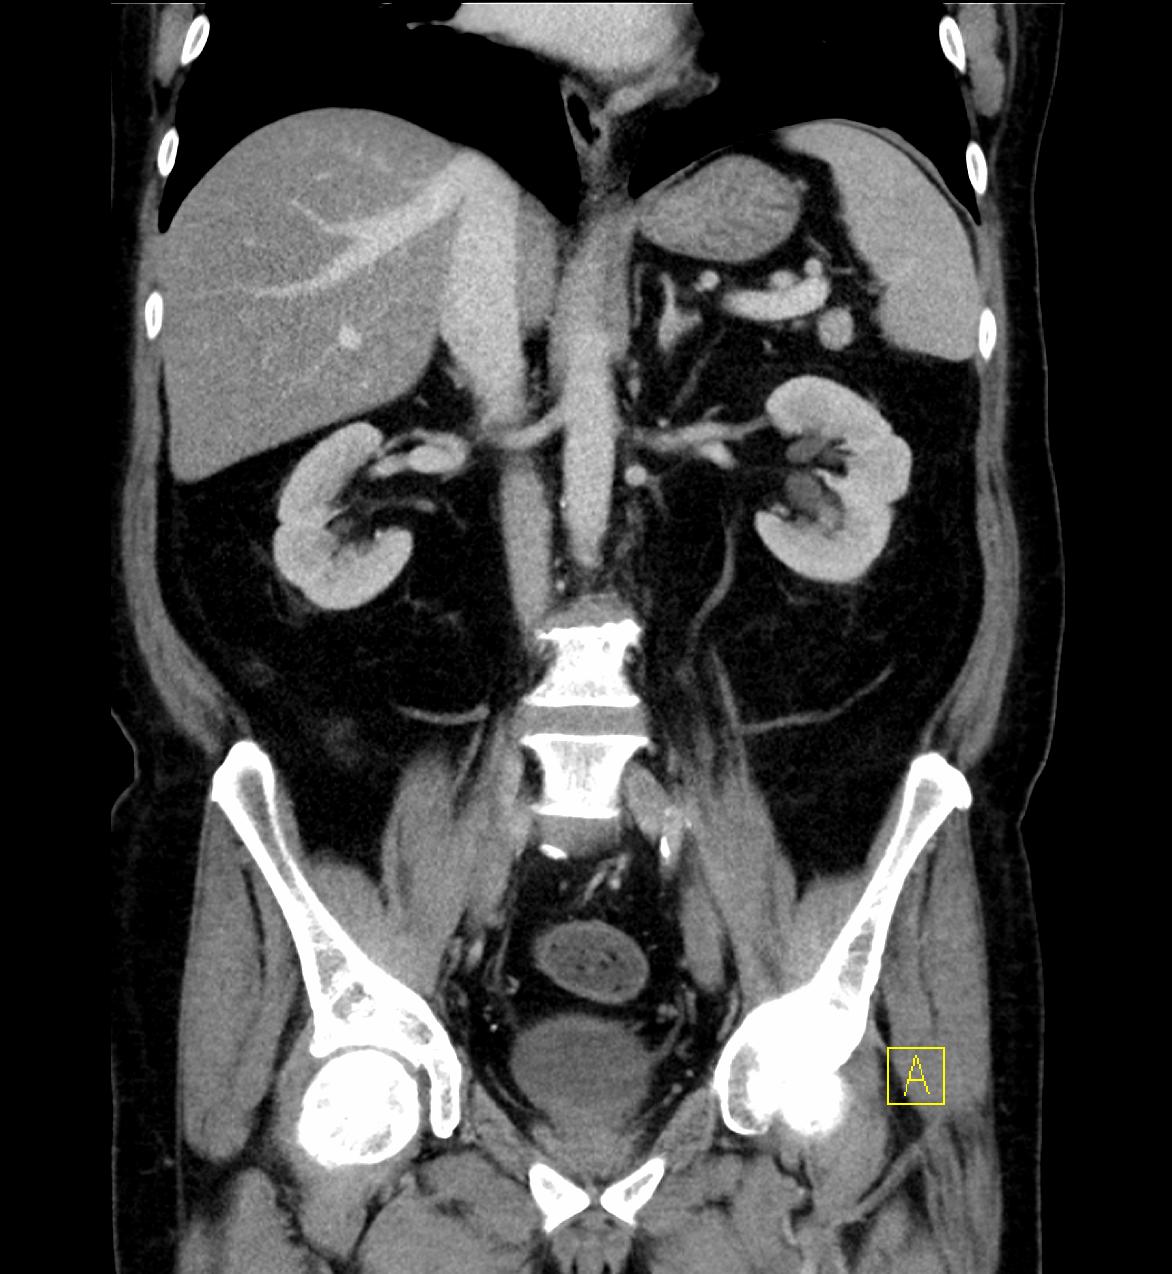

Die PET/CT ist in der Medizin derzeit die modernste zur Verfügung stehende bildgebende Untersuchung in der Diagnostik von Tumorleiden. Sie ermöglicht oft, sehr kleine Herde früher als mit anderen Verfahren wie Kernspintomographie (MRT) oder alleiniger Computertomographie (CT) zu entdecken. Ein besonderer Vorteil des Verfahrens besteht in der Kombination zweier bildgebender Verfahren, die sich perfekt ergänzen. Durch die CT Technik können Körperregionen und mittlerweile auch der gesamte Körper als vollständiger, lückenloser Datensatz erfasst werden. Dadurch entstehen Bilder in bis dahin ungeahnter Schnelligkeit und Qualität. Im PET werden im Gegensatz zum CT in erster Linie funktionelle Stoffwechselvorgänge im Körper dargestellt. Dazu wird Ihnen radioaktiv markierter Zucker (Glucose) in minimaler Menge in eine Vene injiziert. Die Verteilung im Körper wird mit einer speziellen Kamera (PET/CT-Scanner) gemessen, die Schnittbilder des Körpers gewinnt.

Die Glucose wird mit dem Radionuklid Fluor-18 markiert, das eine Halbwertzeit von 110 min hat. Das bedeutet, dass alle 2 Stunden die Radioaktivität um die Hälfte abnimmt. Zusätzlich wird innerhalb der ersten 2 Stunden ein Großteil der Radioaktivität über den Urin ausgeschieden. Insgesamt ergibt sich daraus eine durchschnittliche Strahlenbelastung von 6 mSv. Durch die PET wird also das Doppelte der natürlichen jährlichen Strahlenbelastung verursacht.

Zusammen mit der PET wird in der gleichen Untersuchung eine Computertomographie (CT) durchgeführt. Je nach Fragestellung und wenn schon Voraufnahmen vorhanden sind, wird das CT meist als Niedrig-Dosis CT ohne Röntgenkontrastmittel gefahren, d.h. mit niedriger Strahlenbelastung aber eingeschränkter Erkennbarkeit von anatomischen Details.

Ein Hybridgerät zwischen PET und CT in 64-Zeilen Technik wie am Klinikum Ludwigshafen kombiniert also in idealer Weise die detailgerechte hoch ortsaufgelöste Abbildung morphologischer und funktioneller Krankheitsaspekte insbesondere im Bereich der Onkologie.